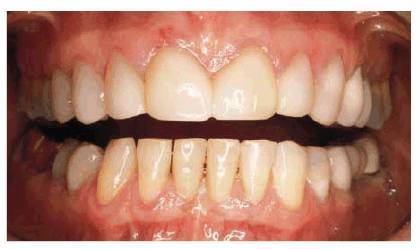

PROBLEM: This 39-year-old individual presented with diastemas between

had a marked overbite and fracture of a mandibular central incisor (Figure 23-4A

Figure 23-4A: This 39-year-old man was unhappy with his diastema, deformed laterals, and mandibular fractured incisor.

TREATMENT: A removable maxillary appliance with finger springs was

constructed to orthodontically reposition the central incisors together (Figure 23-4B). A mandibular lingual appliance

was also used to upright the molars to regain lost vertical dimension and

realign the crowded mandibular anterior teeth. After completion of orthodontic

treatment, the maxillary central incisors were splinted together with composite

resin to prevent future drifting and reformation of the diastema (Figures 23-4C

and D). The

adjacent maxillary lateral incisors were crowned to assist the stabilization of

the central incisors and restore symmetry to the maxillary arch, eliminating

their "peg-lateral" shape (Figure 23-4E). In addition, the mandibular left

central incisor was crowned. The final smile achieved improved esthetics,

health, and function (Figure 23-4F

Figure 23-4B: A removable maxillary appliance with finger springs was used to bring the central incisors together.

Figure 23-4C and D: The maxillary central incisors were bonded together with composite resin to help retain them in their new position.

Figure 23-4E and F: The adjacent maxillary lateral incisors were crowned to help hold the central incisors in place and restore symmetry to the maxillary arch. The mandibular left central incisor also was crowned to complete the esthetic result.

RESULT: The success of this case is based

on a close working relationship with the orthodontist to accomplish necessary

repositioning before restorative procedures are begun. The final esthetic

result could not have been achieved by crowning the four incisors alone. If

orthodontics had not been employed, either the central or lateral incisors

would have necessarily been overcontoured; in addition, the overbite would not

have been corrected to any appreciable extent.